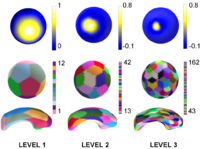

Multiscale Shape Segmentation TechniquesTo represent multiscale variations in a shape population in order to drive the segmentation of deep brain structures, such as the caudate nucleus or the hippocampus. More... |

Wavelet Shrinkage for Shape AnalysisShape analysis has become a topic of interest in medical imaging since local variations of a shape could carry relevant information about a disease that may affect only a portion of an organ. We developed a novel wavelet-based denoising and compression statistical model for 3D shapes. More... |

Multiscale Shape AnalysisWe present a novel method of statistical surface-based morphometry based on the use of non-parametric permutation tests and a spherical wavelet (SWC) shape representation. More... |